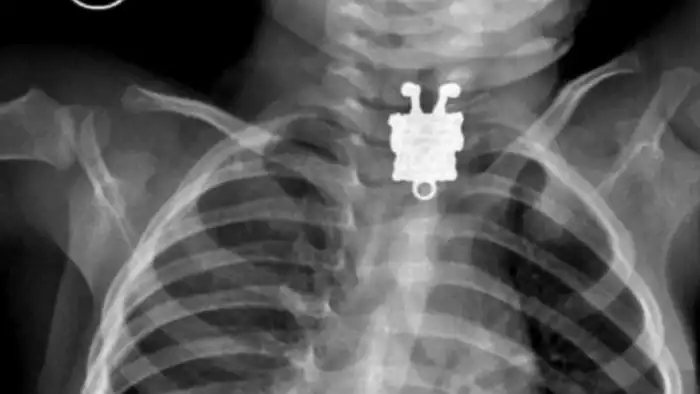

11. Рентгеновский снимок 16-месячного ребенка, проглотившего брелок